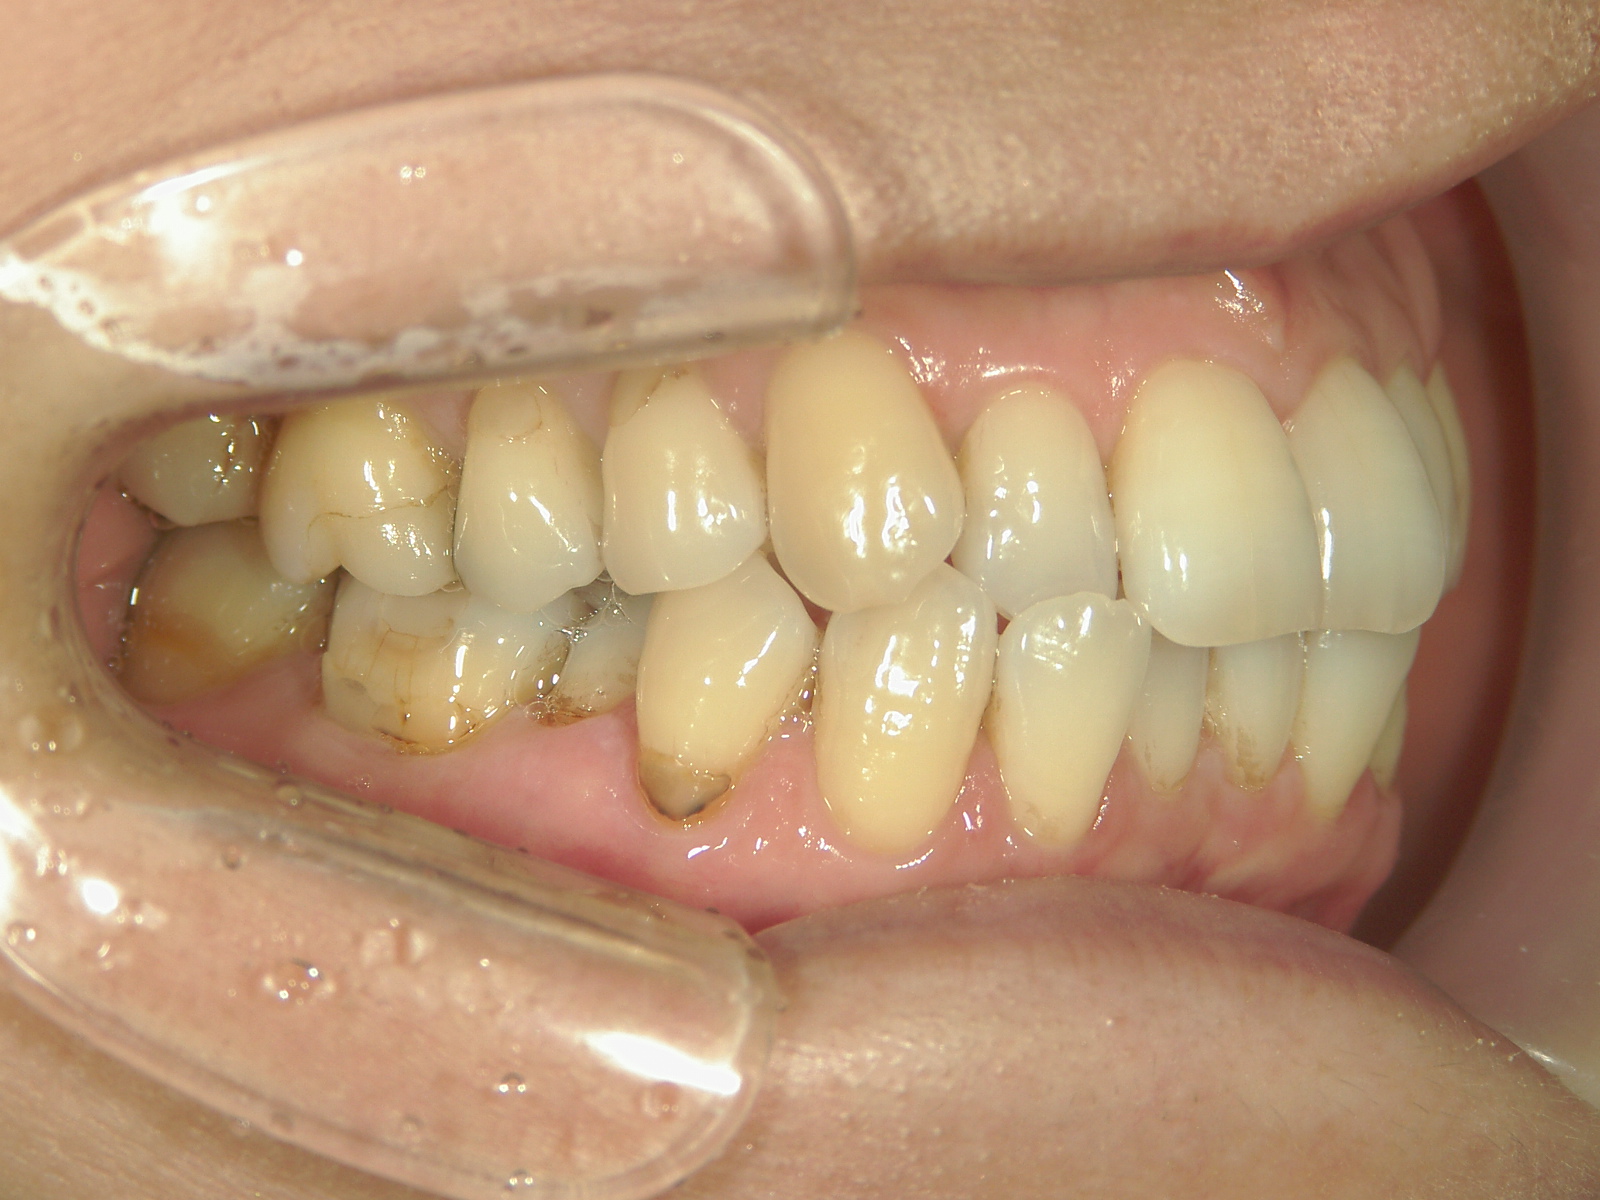

インビザライン矯正 症例(25)

主訴: ㊤前歯が出ていて、噛み合わせが気になる。

カテゴリー : ガタガタ(叢生)